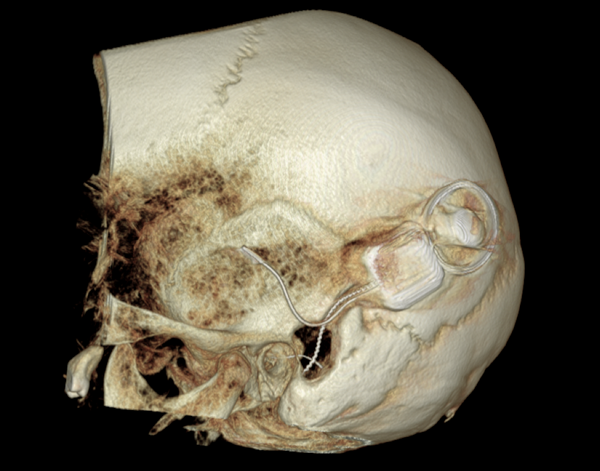

Both patients were imaged immediately with CBCT using SCANORA® 3Dx (Soredex, Tuusula, Finland). The field of view (FOV) was 140 x 165 mm and voxel size 0.2 mm. Imaging parameters were 90 kV, 8 mA, 4.00s. Standard 1 mm axial, coronal and sagittal reformations were made, as well as MIP and 3D reconstructions using OnDemand3D™ software (Cybermed, Seoul, South Korea).

CBCT proved to be optimal for imaging of these implants because of the superior bony delineation and nearly artefact free images. All four parts, i.e. the receiver stimulation part, extracochlear electrode implanted on the surface of the temporal bone, the extracochlear electrode plate and the intracochlear electrode array could be well imaged with CBCT.

On CBCT all four of the important parts of the implant were very well seen both on the axial slices and three dimensional surface reconstruction images. The implant is placed on magnetic plates, and the extracochlear part was seen in an abnormal separated position. The intracochlear electrode array showed no signs of separation in either of the cases. The intracochlear electrodes were well seen in both of the cases.

The optimal images of these two patients are shown in the radiographic illustrations in Figures 1-7.

Figure 3: 3D reconstruction image of patient 1.

Figure 5: 3D reconstruction image of patient 2.